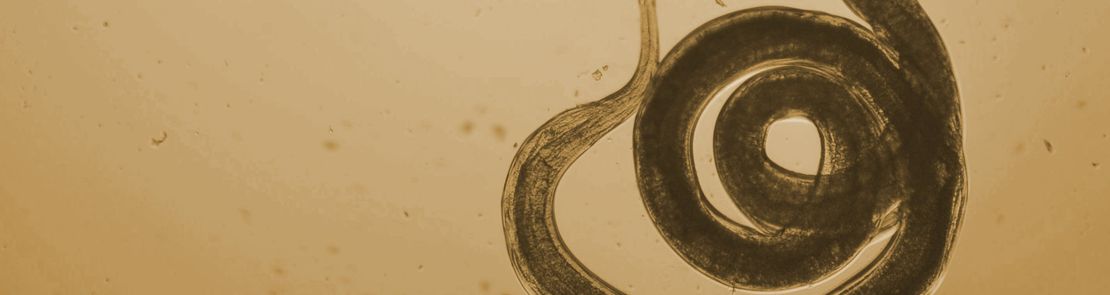

Female Cooperia MRI

The new sections, covering round worms, lungworm, liver and rumen fluke and ectoparasites such as flies, lice and ticks, provide a sound basis for advice for farmers and their advisers.